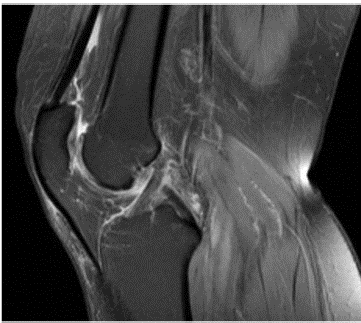

Mujer de 60 anos con antecedentes personales de miopía magna, apendicectomía y condrocalcinosis en forma artrósica de larga data asociada a hipomagnesemia en seguimiento por Reumatología. Desde la adolescencia refería cierta debilidad y molestias articulares que requirieron seguimiento reumatológico, siendo detectada una hipomagnesemia y condrocalcinosis artrósica de rodilla izquierda (fig. 1). En tratamiento domiciliario con calcio oral y suplementos de magnesio de forma intermitente. Tras un episodio de coledocolitiasis, fue intervenida de colecistectomía, reiniciando al alta de dicho ingreso el tratamiento de forma parcial, sin suplementación de magnesio. Tras el alta, la paciente acudió a Urgencias por debilidad generalizada, sin otros síntomas asociados, presentando estabilidad hemodinámica en todo momento con tensión arterial normal. En la analítica realizada se detectó hipopotasemia e hipomagnesemia. Tras iniciar tratamiento sin mejoría, se decidió ingreso en Nefrología para estudio y ajuste de medicación. Como otros datos a destacar, la paciente presentaba una alcalosis metabólica con pH 7,52 y bicarbonato 29 mmol/L, potasio (K) 2,9 mEq/L, magnesio (Mg) 1,03mg/dl, calcio 9,9mg/dl, hemograma normal. En muestra aislada de orina presentó hipocalciuria con calcio 2 mg/dl, cloro 45 mEq/l, sin albuminuria.